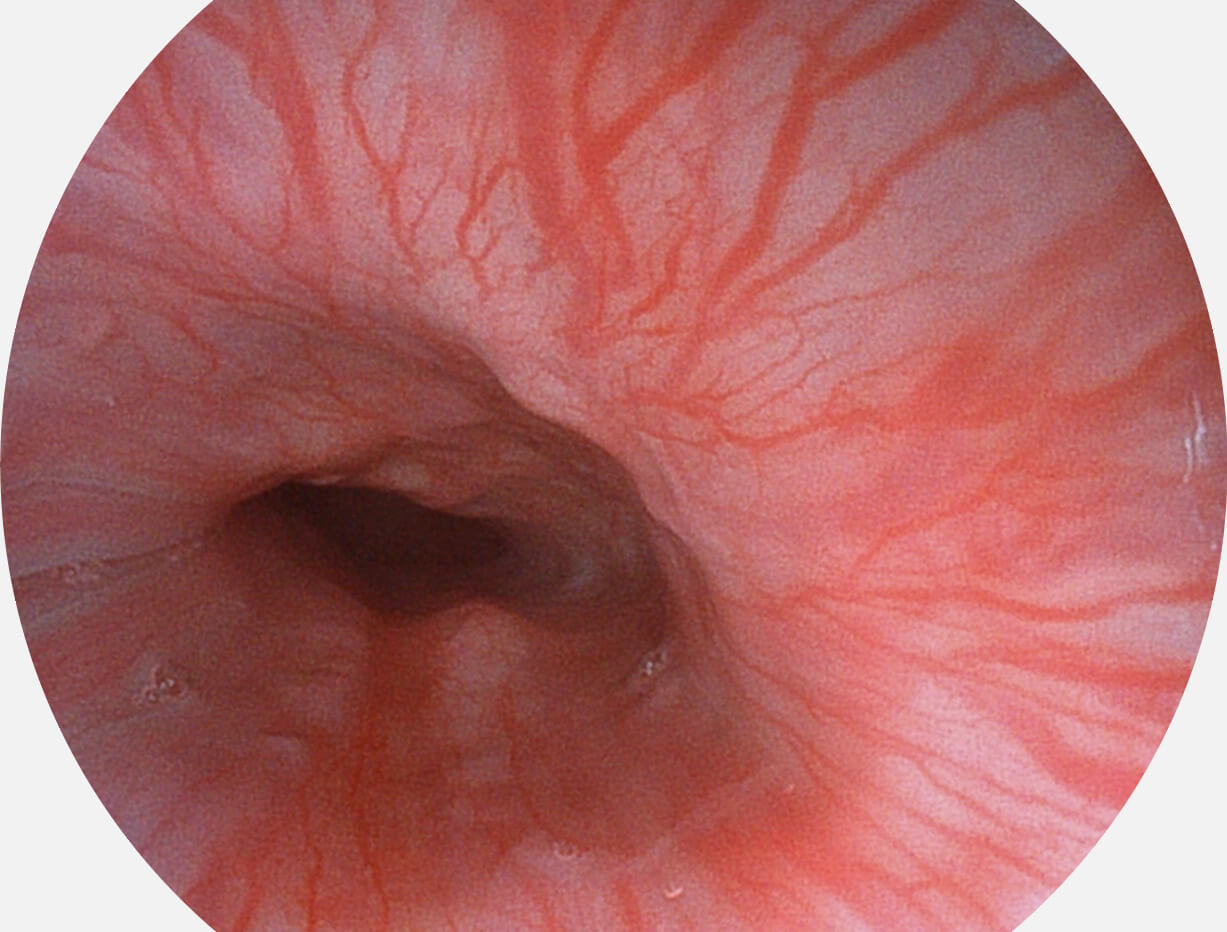

白光图像